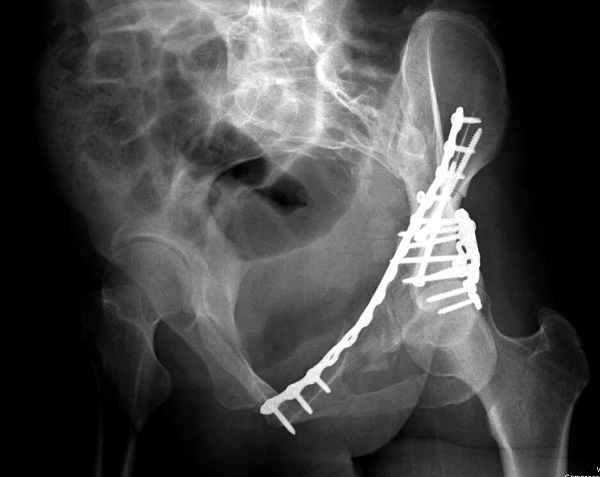

Интересно было бы посмотреть рентгенограммы до операции. У меня впечатление, что я не все вижу, что тут есть... Уважаемые Господа "тазисты" и "тазологи", к какому типу переломов вертлужной впадины по Летурнелю вы бы отнесли это случай?

Из переломов проходящих через крыло и/или заднюю стенку ни простой перелом "передней колонны" (явно имеется пером задней стенки, и не видно перелома седалищной или лонной), ни простой "поперечный", ни ассоциированный "Т-образный" (т.к есть перелом крыла и не видно перелома седалишной), ни ассоциированный "задняя колонна+задняя стенка", на ассоциированный "поперечный+задняя стенка", ни ассоциированный "передняя колонна+задняя гемисфера" (не видно перелома седалищной), ни ассоциированный "обе колонны" (не видно перелома лонной седалищной) не подходят под эту классификацию....

>Вопрос к знатокам: Так что это?

к таковым себя не причисляю, но...обычное дело для нашей страны - выкладывать 3D и не показывать стандартные проекции Judet. Дигност представляет те ракурсы, которые по-его мнению наиболее информативны, более того комп сам достраивает какие-то мелкие повреждения по 3D по своему усмотрению. По данной реконструкции можно предполагать высокий двухколонный перелом с оскольчатыми передней и задней колоннами, оскольчатую высокую переднюю колонну с задним полупоперечником или одно из перечисленных с вовлечение КПС. У меня впечатление за второй вариант, но нужно обследовать нормально - проекции, сканы.

высылаю дополнительно сканы.

итак, второй вариант: высокий двухколонный с вовлечением КПС... Ни одно из основных повреждений не репонировано, кроме задней стенки. Скорее всего попытка реконструкции вертлуги сейчас будет очень травматичной и не очень эфективной, т.е. вероятный риск более значим, чем ожидаемая польза... Лучше подождать, и потом сразу эндопротез

Когда перелом не получается отнести к какому либо типу - эффективнее всего описать более детально. В дальнейшем проще бывает сортировать, и что важнее - "руководство к действию" бывает более обоснованным. В данном случае графа клинического диагноза может выглядеть так: Застарелый разрыв правого крестцово-подвздошного сочленения, консолидирующиеся со смещением переломы крыла и тела правой подвздошной кости, обеих колонн и задней гемисферы правой вертлужной впадины. Состояние после остеосинтеза.